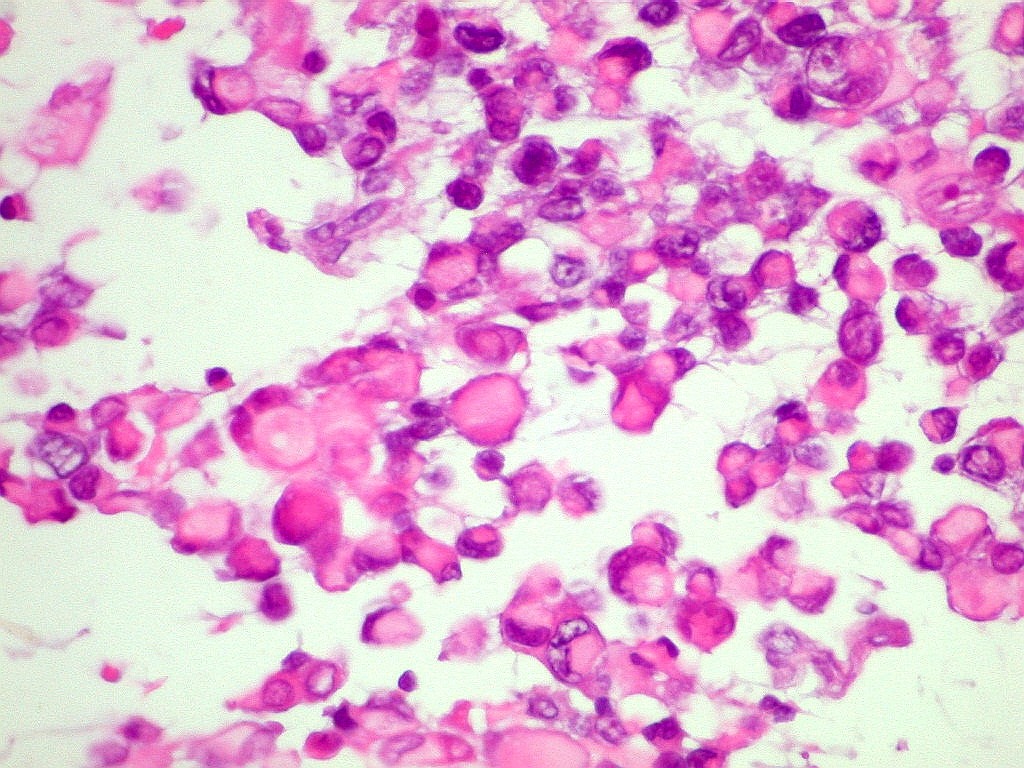

| CD34.

Positivo nos vasos, negativo no tumor |

Ki67.

Marca cerca de 90% dos núcleos neoplásicos, indicando altíssimo

índice proliferativo. |

p53.

Marca a totalidade dos núcleos neoplásicos, sugerindo mutação

do gene P53, que regula apoptose. |